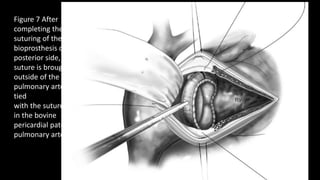

Figure 7 After

completing the

suturing of the

bioprosthesis on the

posterior side, the

suture is brought

outside of the

pulmonary artery and

tied

with the suture used

in the bovine

pericardial patch for

pulmonary artery.

Figure 8 The anterior aspect of

bioprosthesis is now sewn to the

bovine pericardial patch using 4-0

prolene suture